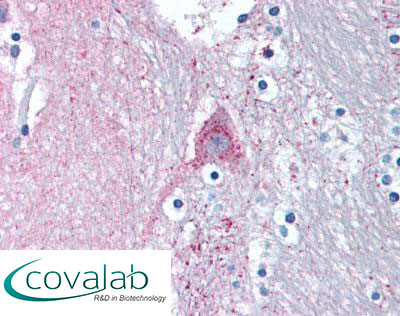

Anti-MARK1 antibody IHC staining of formalin-fixed, paraffin-embedded human caudate after heat-induced antigen retrieval.